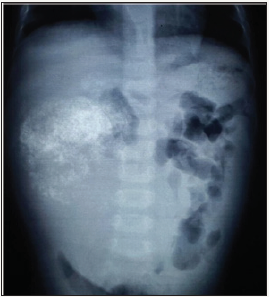

One and half-year-old boy was brought to us with a progressively increasing right-sided abdominal lump noticed since last 7 months. There was no other associated constitutional complaint. On examination, patient had stable vitals but gross pallor. Abdominal examination revealed a 15x15cm firm, immobile, non-tender mass with lobulated surface with ill-defined margins in the right lumbar, right hypochondriac, epigastric, umbilical and right iliac fossa regions. Liver margin could not be palpated separately. Rest of the systemic examination was normal. Investigations revealed severe anaemia with (Hb 3.4gm/dl). His renal and liver function tests were essentially normal with slight rise in AST level of 183 U/l. X-ray abdomen showed coarse calcifications in the area of the mass (Figure 1). Ultrasonography (USG) revealed a large solid lesion in right lumbar region with coarse calcification and vascularity; organ of origin could not be estimated accurately. Liver showed two target lesions in segment VII and VIII. Contrast enhanced computerised tomography (CECT) showed 11.5x9 cm predominantly exophytic, mildly enhancing mass lesion of having solid and cystic components having large calcifications; there were ill-defined planes between the mass and inferior margin of right lobe of liver (Figure 2 & 3). The mass was attenuation inferior vena cava posteriorly and displacing the portal vein superiorly, however both the vessels showed normal contrast opacification. The liver measured 12cm with a well-defined mildly enhancing lesion in superior segment of right lobe. Rest of the abdominal structures including spleen, bilateral kidneys, pancreas and thorax were normal. No abdominal lymphadenopathy or free fluid was noted.

Figure 1: X-ray abdomen showing coarse calcifications in the area of the mass.